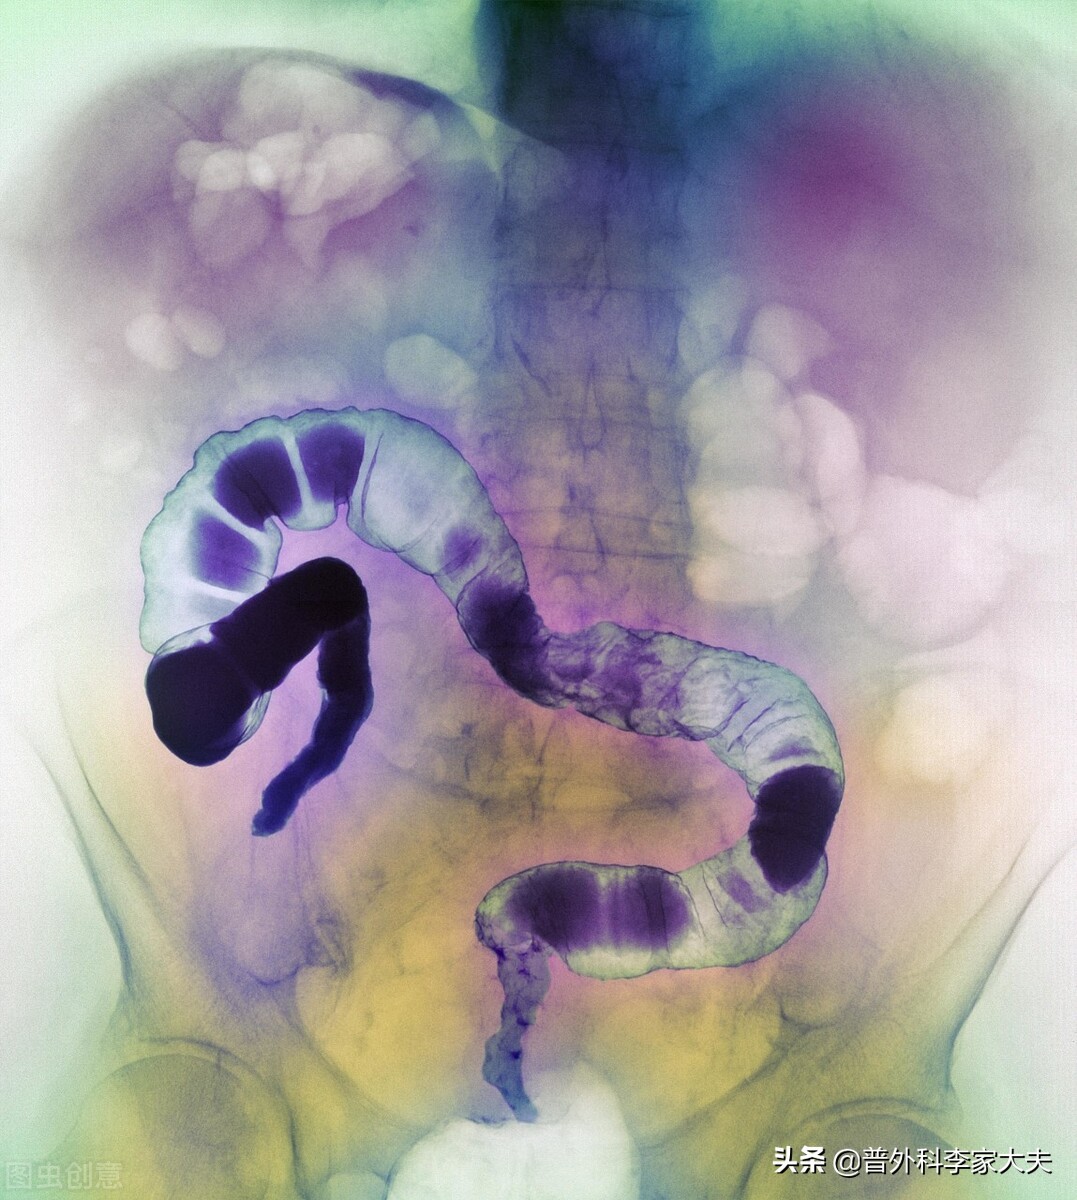

直肠癌

手术

超声检查